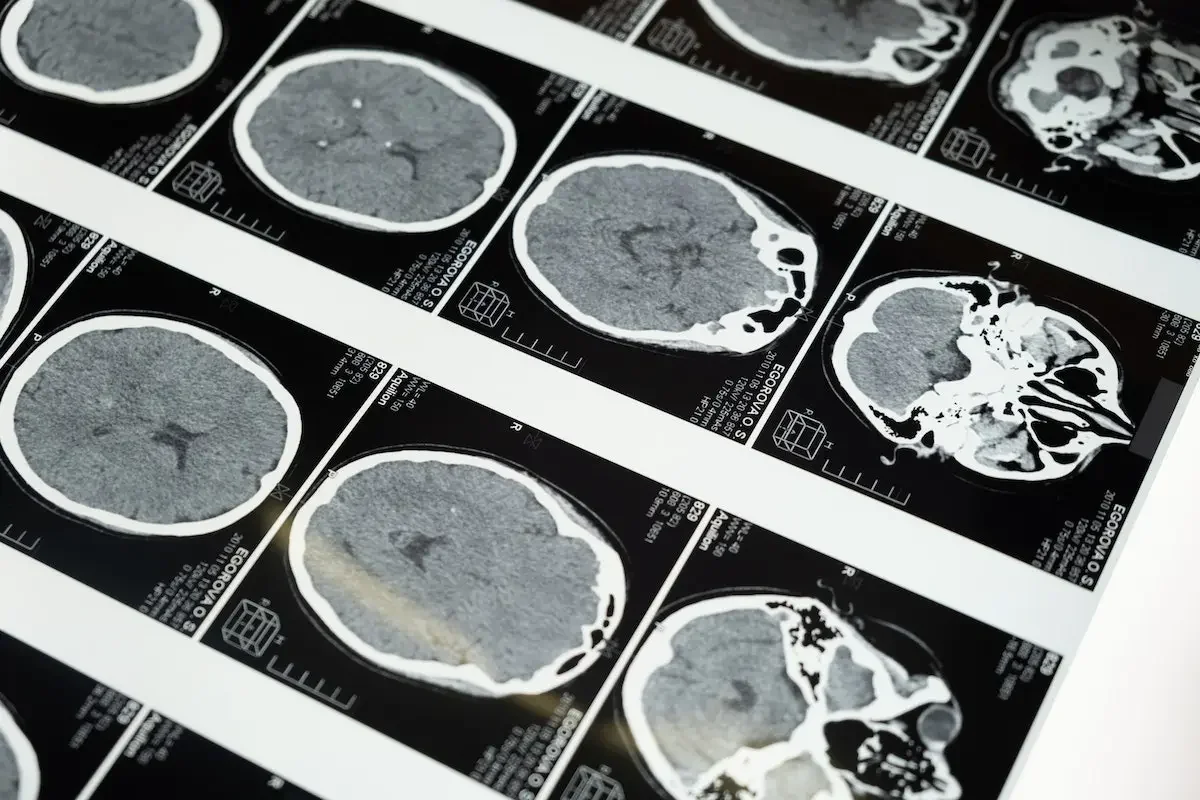

The intriguing aspect of HBOT lies in its multifaceted impact on the body. When individuals are exposed to mold toxins, various neurophysiological abnormalities can occur, affecting brain functions. HBOT, in its essence, significantly increases oxygen concentration in all body tissues, even in areas with limited or blocked blood flow. This boost in oxygen supply triggers the growth of new blood vessels, enhancing circulation in regions with compromised blood flow.